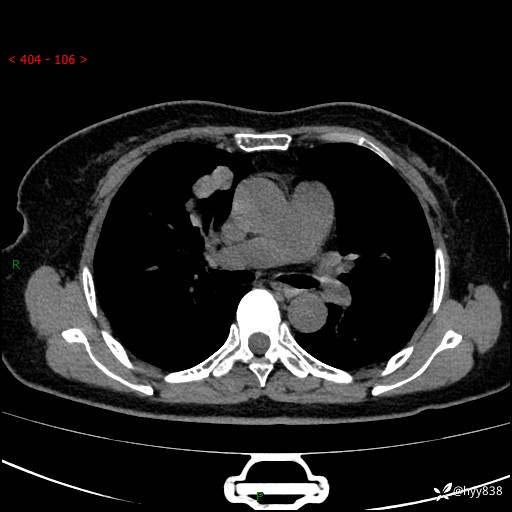

70岁/女,发现右上肺肿物10天。患者过敏体质,只有平扫,错过了一定可惜---结果公布~

【患者信息】:70岁/女

【主诉】:发现右上肺肿物10天

【现病史及既往史】:者10天前因“背部酸痛”于当地治疗,无发热,无呕吐,无头痛头晕等不适,胸部CT示右上肺肿物。遂来我科就诊,门诊看过病人后以“”收入我科, 自患病以来,精神、饮食、睡眠尚可,大小便正常,体力体重无明显减轻。

【检查】:胸部CT平扫(患者过敏体质,不能增强)